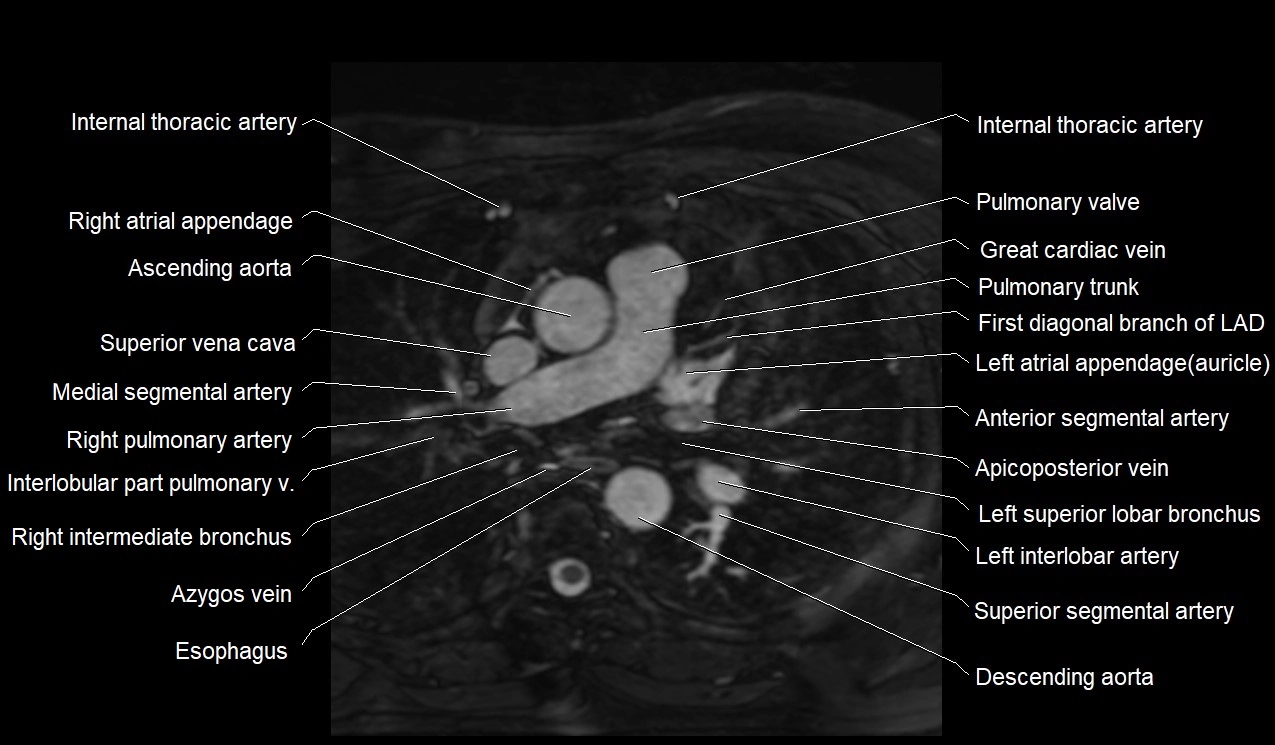

MRI image